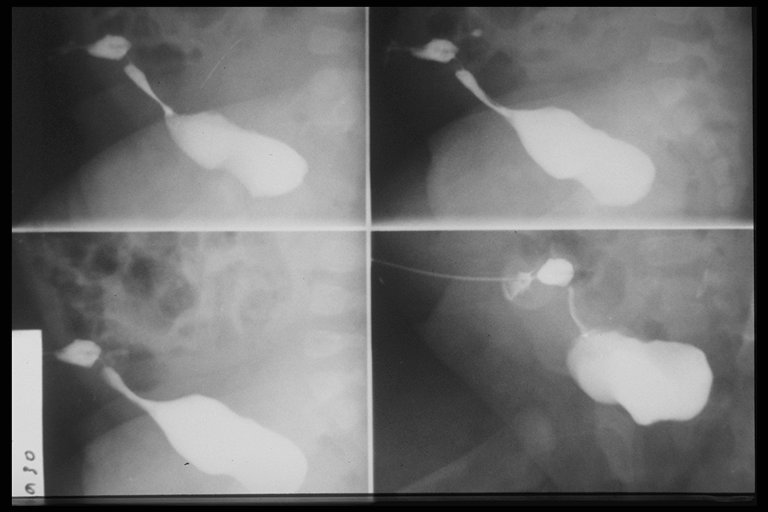

Fistulogram demonstrates the tract connecting the umbilicus and the urinary bladder

Fistulogram demonstrated the tract connected between the umbilicus and the intestine

Fistulogram in a child with umbilical hernia and fistula demonstrates the connection to the intestine